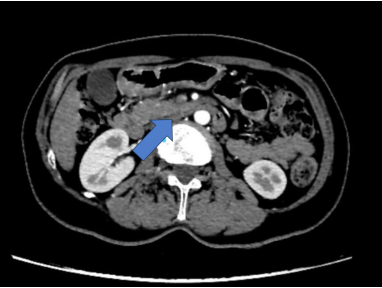

La ecografía abdominal inicial mostró una vesícula sin litiasis en su interior, sin dilatación de la vía biliar intra y extrahepática, y un páncreas de forma y tamaño conservado. Ante la persistencia de la sintomatología se indicó una TC de abdomen y pelvis, con hallazgos de páncreas de tamaño, contornos y densidad normal, pero en el cuerpo se identificaba una imagen hipodensa redondeada, de 12,8 mm de diámetro, de contornos levemente lobulados, aspecto quístico y, al parecer, en comunicación con el conducto pancreático principal (Figura 1), el cual se encontraba discretamente dilatado en toda su extensión, con un diámetro de 3 mm, y emergía directamente a la segunda porción del duodeno, configurando páncreas divisum como variante anatómica (Figura 2).